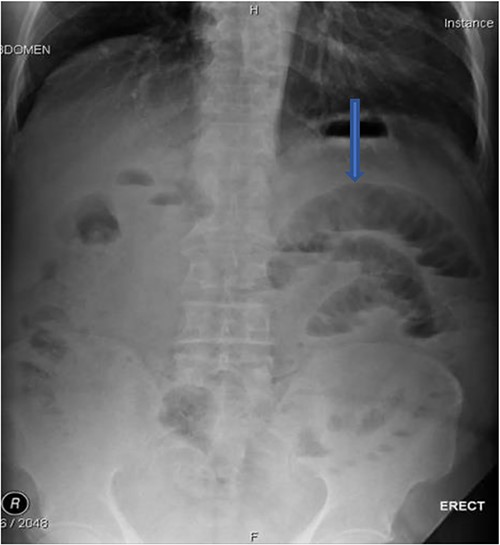

The plain film of the abdomen showed multiple air-fluid levels on the erect film (Fig. 1) and small bowel dilatation on the supine (Fig. 2). The CT showed multiple air pockets in the biliary tree, representing pneumobilia (Fig. 3). It also showed evidence of a circular radio-dense stone measuring 2 cm within the distal jejunum, leading to obstruction and dilatation of the proximal jejunum (Fig. 4).

CT is the investigation of choice. Plain films can reveal dilated small bowels, confirming small bowel obstruction [8]. The presence of Rigler’s triad on the plain film, which includes pneumobilia, dilated bowel, and ectopic gallstones, is diagnostic of gallstone ileus, but this occurs only in 9%–14% of patients [7]. Most patients require surgical intervention to relieve the obstruction. Surgery includes enterotomy and removal of the stone (enterolithotomy) or enterolithotomy with cholecystectomy and repair of the fistula [2]. Commonly, simple enterolithotomy is favored as it carries less morbidity, with or without cholecystectomy at a later date [9]. Spontaneous fistula closure occurs in up to 50% of cases [7].